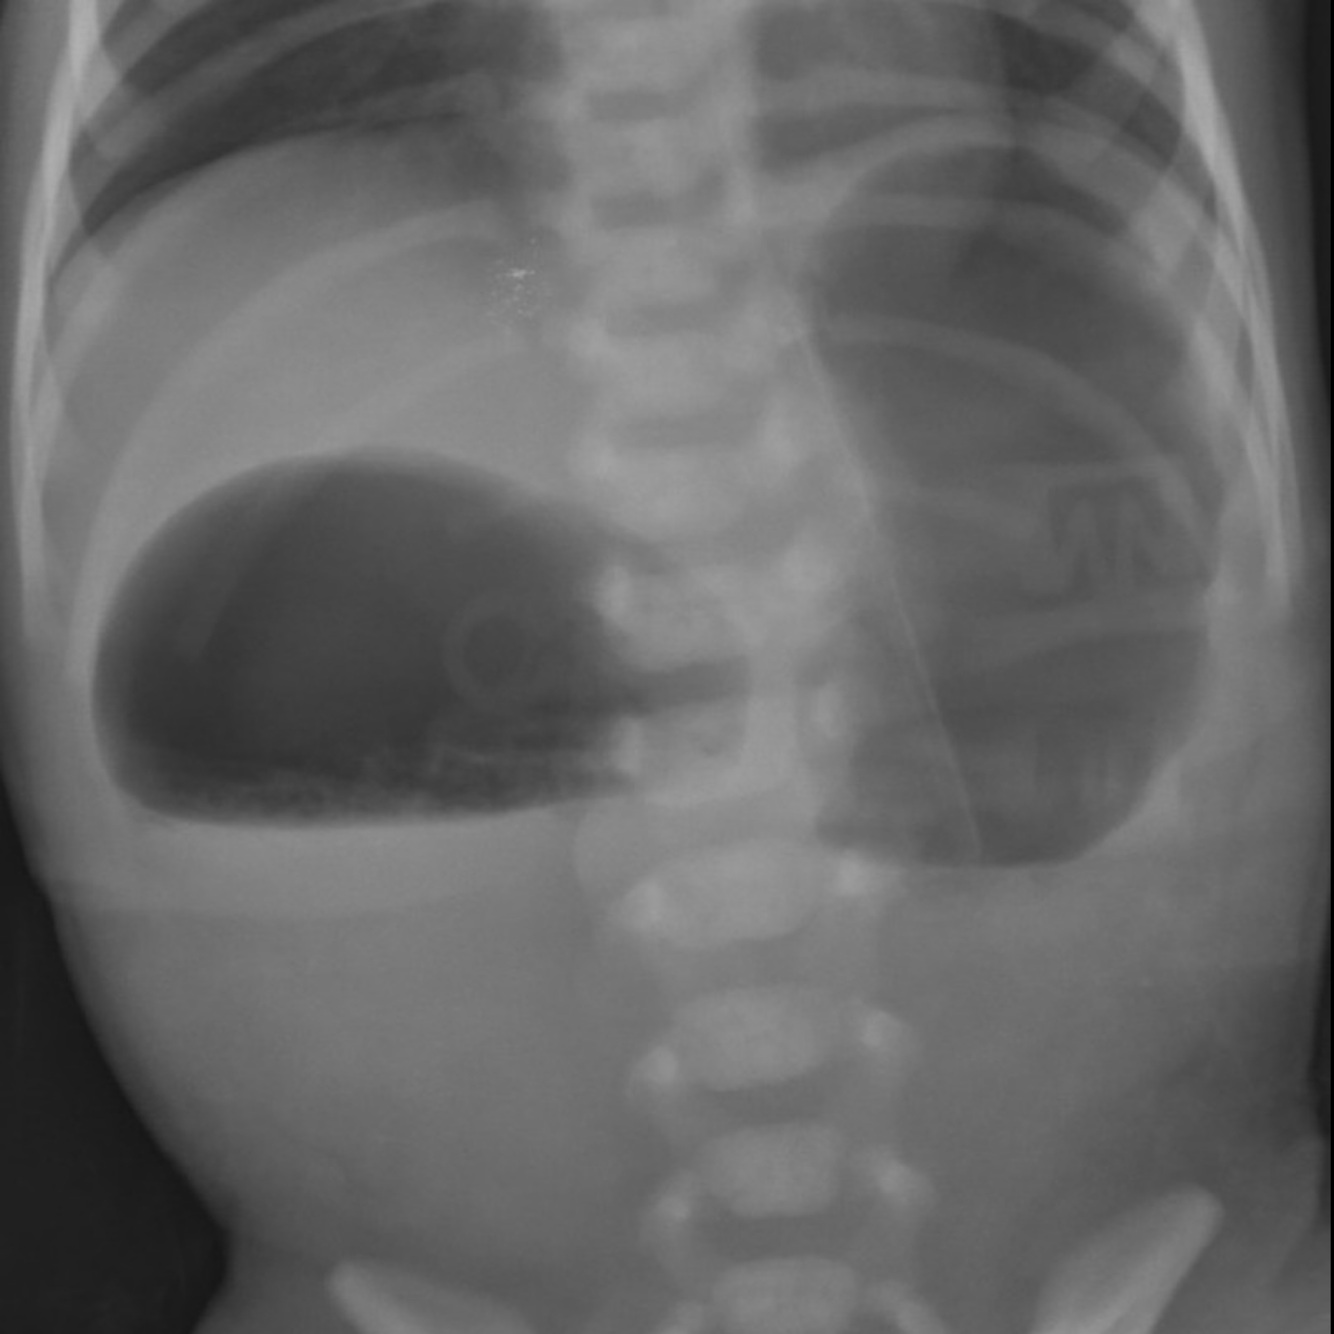

Duodenal atresia : double bubble

small bowel obstruction. Dilated loops of small intestine, seen in the x-ray image of the abdomen,